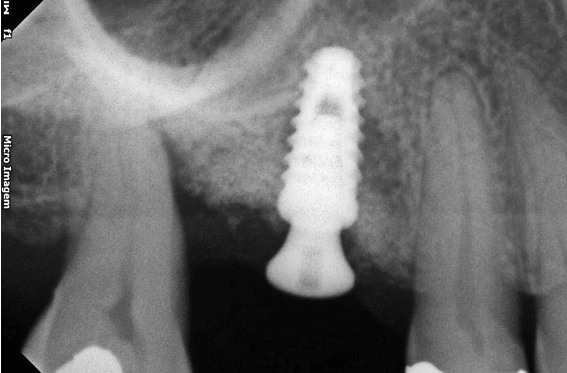

A preservação do alvéolo é uma opção de tratamento, evitando ou reduzindo a perda óssea. Alguns procedimentos são sugeridos com o objetivo de reduzir essa perda fisiológica, como a utilização de biomateriais preenchendo o alvéolo, barreiras, instalação de implante imediato entre outros. 4

Avaliamos o desempenho do biomaterial de hidroxiapatita com colágeno tipo I (Extra Graft XG-13®) na manutenção do volume alveolar.

A aplicação como o caso clínico abaixo se mostrou uma técnica acessível a todos cirurgiões dentistas, pois se trata de um procedimento de simples execução e acessível. Logo, deveria constar na clínica diária.